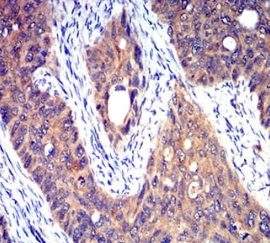

HTR3A Mouse Monoclonal antibody[3B11]

The product of this gene belongs to the ligand-gated ion channel receptor superfamily. This gene encodes subunit A of the type 3 receptor for 5-hydroxytryptamine (serotonin), a biogenic hormone that functions as a neurotransmitter, a hormone, and a mitogen. This receptor causes fast, depolarizing responses in neurons after activation. It appears that the heteromeric combination of A and B subunits is necessary to provide the full functional features of this receptor, since either subunit alone results in receptors with very low conductance and response amplitude. Alternatively spliced transcript variants encoding different isoforms have been identified.

Immunogen:    Purified recombinant fragment of human HTR3A (AA: extra 24-157) expressed in E. Coli.

IHC    1/200 - 1/1000